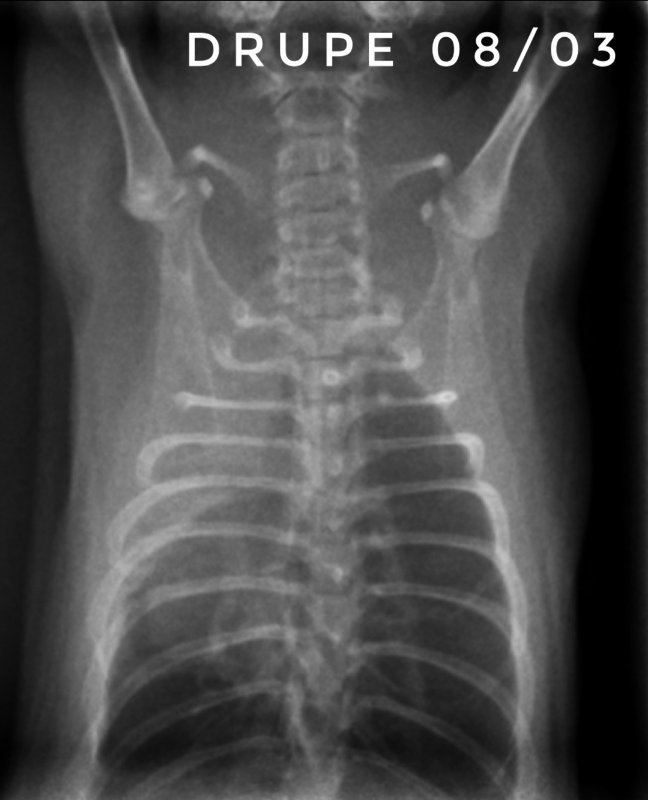

Toujours pour ceux que ça intéresse, les dernières  radios et le suivi du poids (Pyridion a commencé à perdre du poids le 04 mars, traitement changé le 08)

Bon, faudra que je vous remonte les radios de ce jour...

Il nous reste donc 3 malades : Drupe, Caryopse et Pyridion.

Drupe va vraiment mieux, poumons encore touchés mais mieux quand même (mais décidément c'est bien long).

Pyridion a eu un vrai mieux la semaine dernière et grosse dégradation là. Les radios n'ont pas bougé depuis 3 semaines...

Et Caryopse, mon petit nain (180g) va physiquement pas trop mal, c'est à dire qu'il respire vite mais pas pire quoi... par contre ses radios sont... bref, le veto ne s'y attendait pas du tout lui non plus... en gros, petit mieux là où il était touché avant mais dégradation asur le reste du poumon...